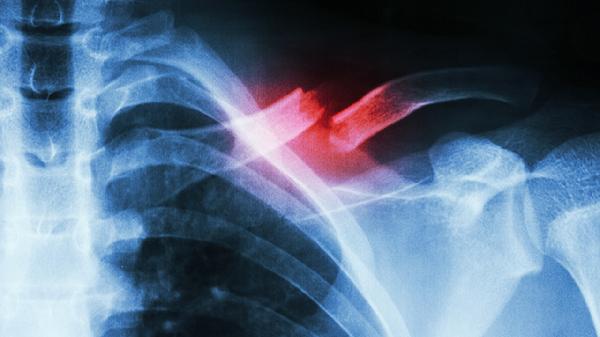

X光检查操作简便且费用较低,能够清晰显示骨骼的形态变化和骨质破坏情况,对骨折、骨增生或钙化等病变有较高诊断价值。对于骨肿瘤的早期筛查和初步定位具有重要作用,尤其适用于骨质破坏明显的病变。但X光对软组织和骨髓腔的显示效果有限,难以评估肿瘤对周围肌肉、神经血管的侵犯程度。